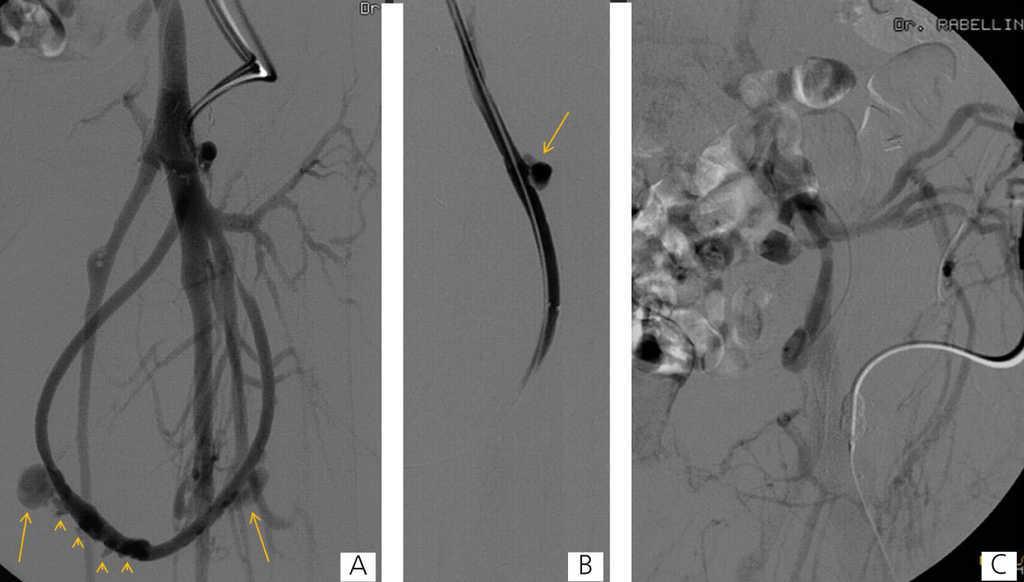

Here we present the case of a 46-year-old patient with chronic renal failure, on trimestral haemodialysis for 23 years secondary to obstructive uropathy, with a left femoral loop (21 months of use) with occluded iliac venous drainage that produced oedema in the leg and three pseudoaneurysms in the therapeutic range. One of these was actively bleeding. The three pseudoaneurysms and occlusion of the left primitive iliac vein were treated using endovascular methods under local anaesthesia. The actively bleeding pseudoaneurysm was excluded with a covered stent, and the other two were percutaneously embolised using balloon-assisted thrombin injections in order to avoid thrombosis in the prosthesis. The iliac venous axis was recanalised and treated with angioplasty balloons; in the final angiographic controls, we observed no pseudoaneurysms, with patency of the prosthesis, iliac venous drainage, no signs of collateral circulation, and without having produced any complications.

Figure 1. Fistulographies